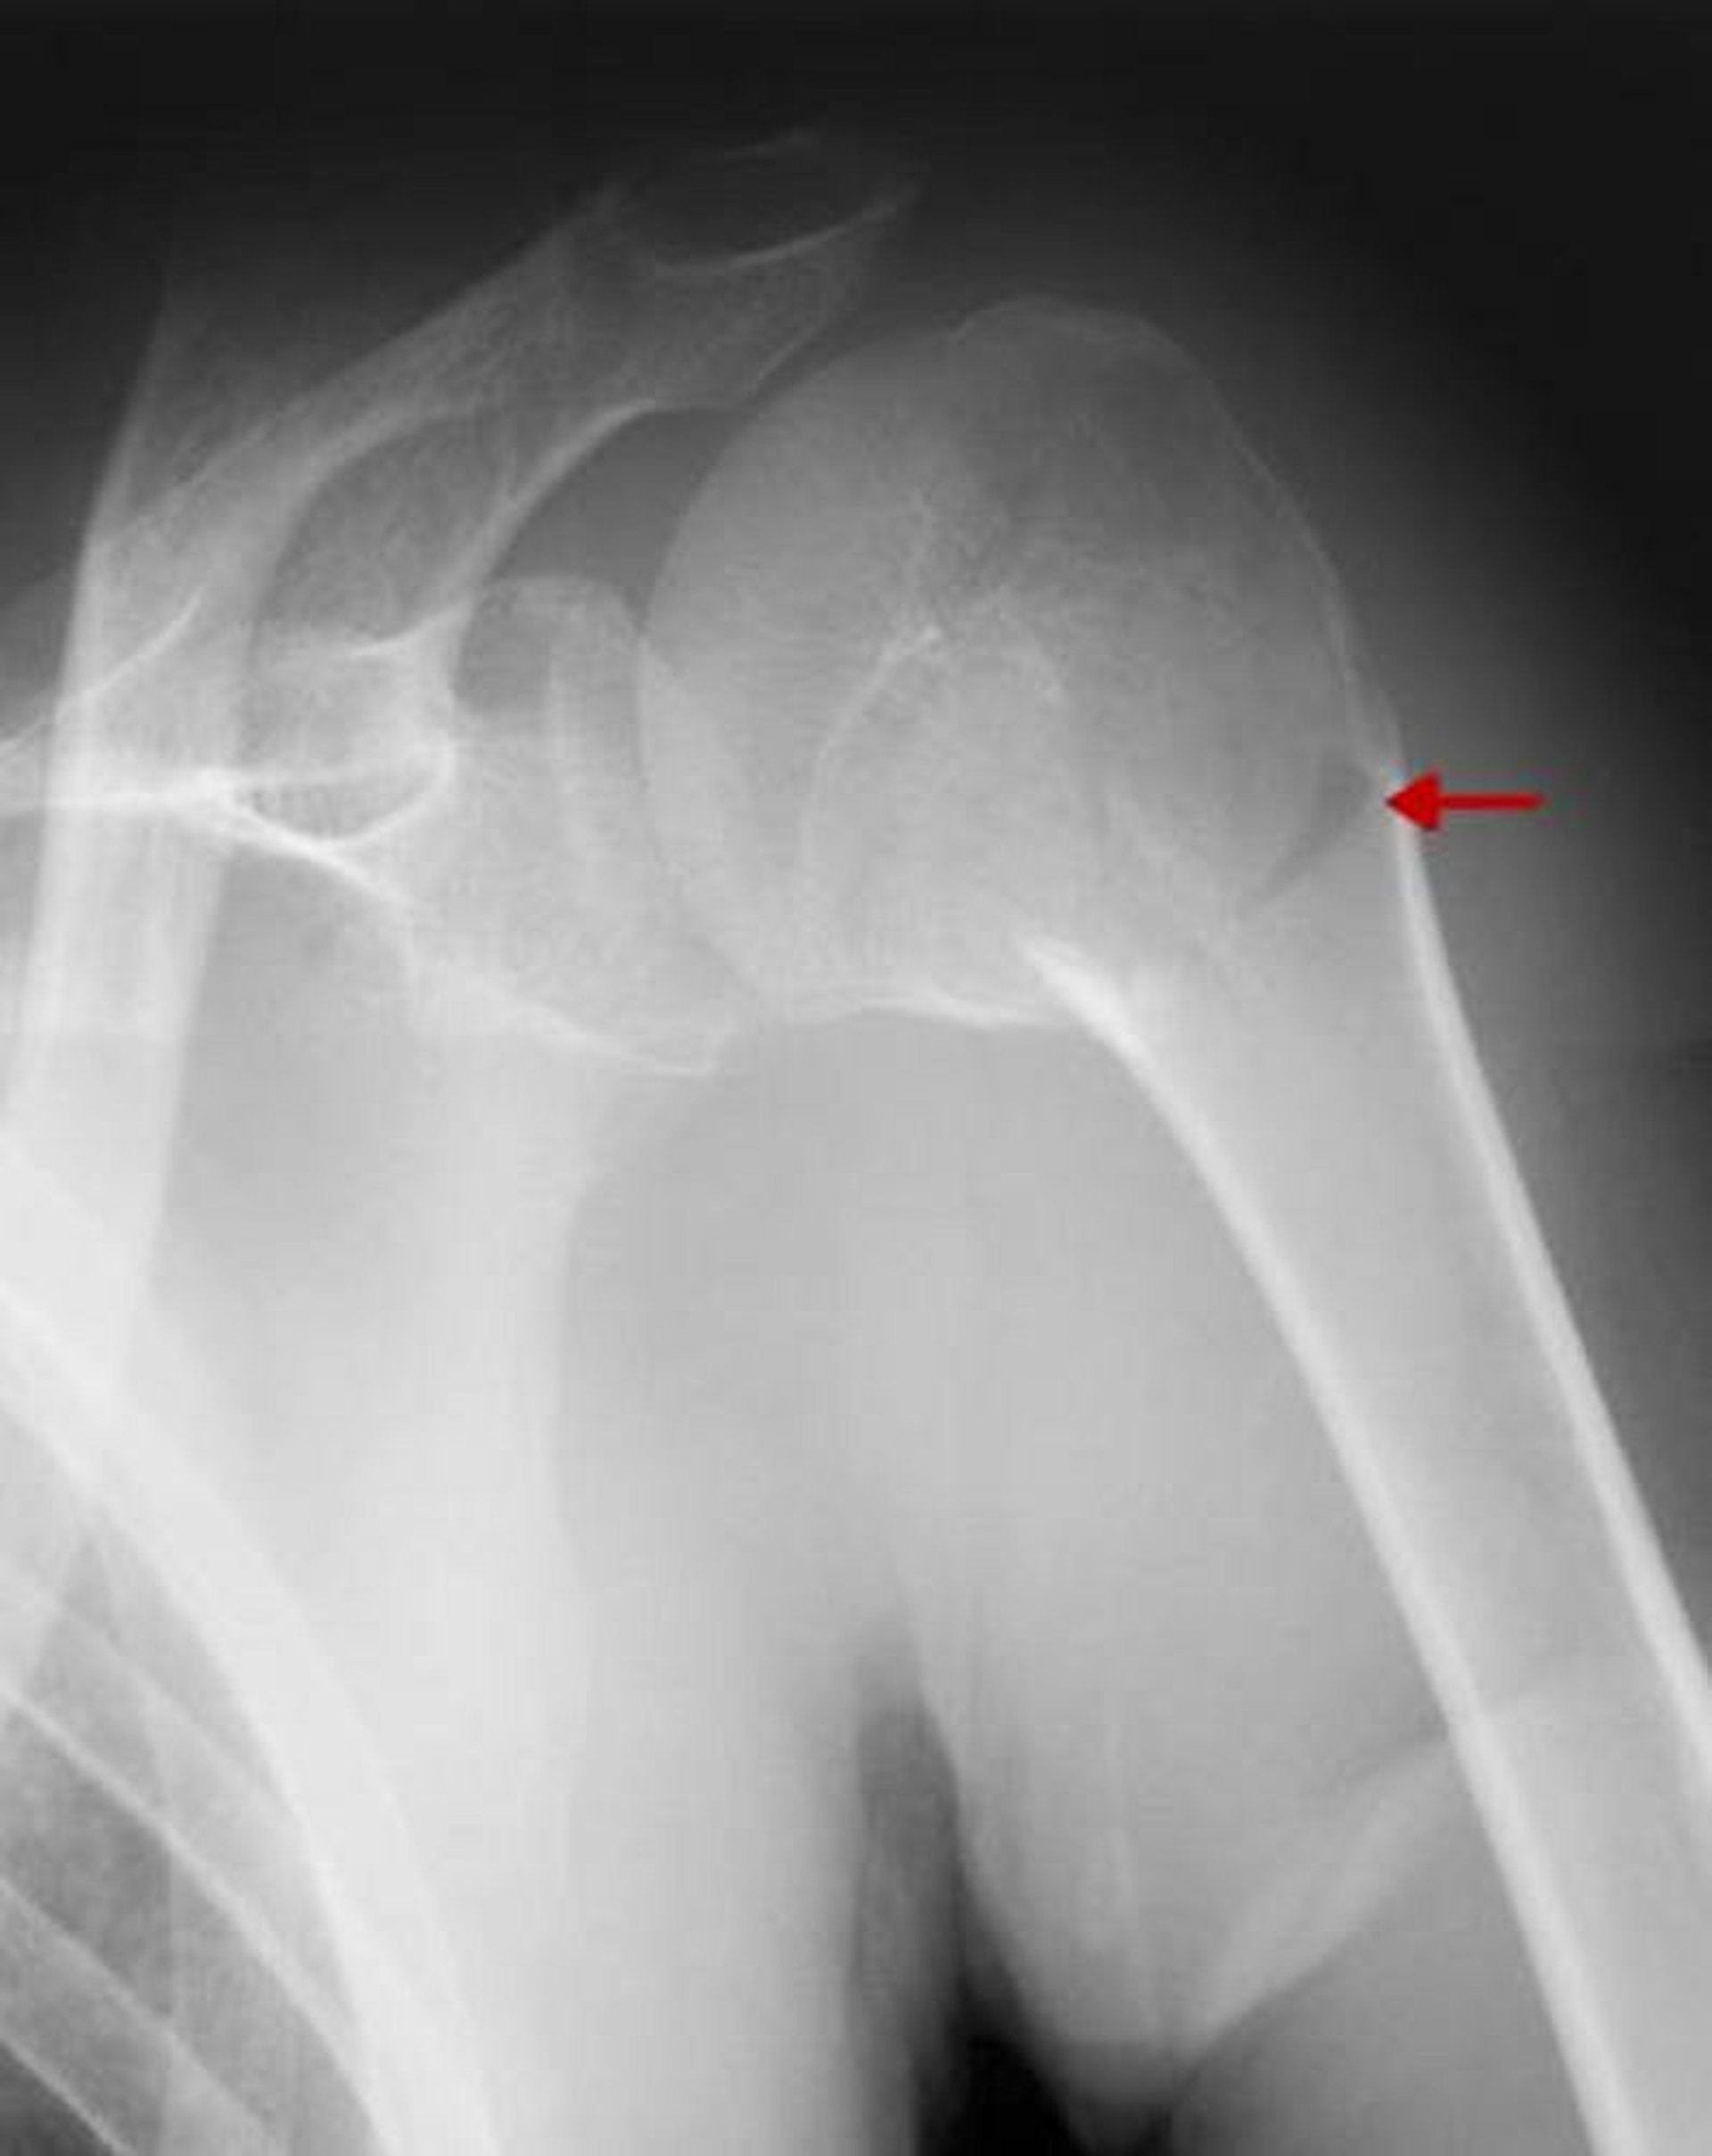

Fractura proximal del húmero

Esta fractura afecta el cuello quirúrgico. Debido a que no hay desplazamiento significativo o angulación > 45°, es una fractura de una parte.

ZEPHYR/SCIENCE PHOTO LIBRARY